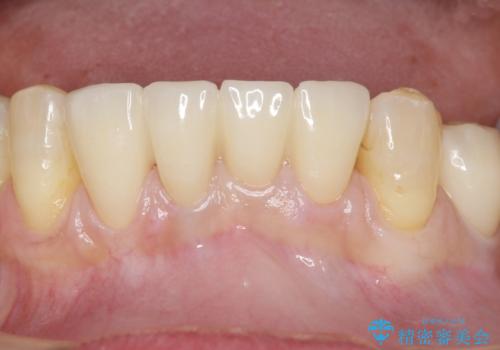

自然な仕上がりに喜んで下さいました。

クラウンを連結することにより気にされていた動揺もなくなり、安心して頂けました。

被せ物の種類:オールセラミッククラウン スタンダード